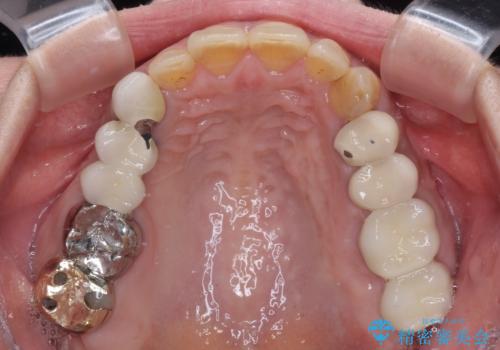

インプラントや歯周外科処置を用いた奥歯の補綴治療

- 下顎の左右奥歯が痛みがあり、噛めないとのことで来院された患者様です。

左右ともに歯根が破折しており、抜歯が必要であったため、抜歯後にインプラント補綴治療を行うこととしました。

左側は骨欠損が著しいことが予想されるため、骨造成術並びに歯肉移植術を併用することとしました。

左上は当初治療予定ではありませんでしたが、クラウンの周りに汚れがたまっていることが気になってきたため、追加して治療を行うこととしました。

歯肉縁下にまで虫歯が及んでいたため、歯冠長延長術を行い、清掃性の改善を試みます。

仮歯がない状態を極力避けたいとのことで、外科処置を少しずつ進めていくことになり、治療期間は2年間を要しました。

治療後は痛みなどなく、快適に噛めるようになりました。